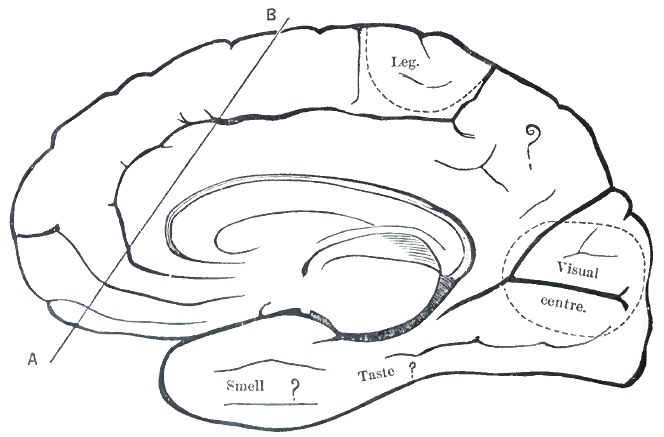

| 10. | DIAGRAM OF THE LATERAL ASPECT OF THE CEREBRAL HEMISPHERE |

| 11. | DIAGRAM OF THE MESAL ASPECT OF THE CEREBRAL HEMISPHERE |